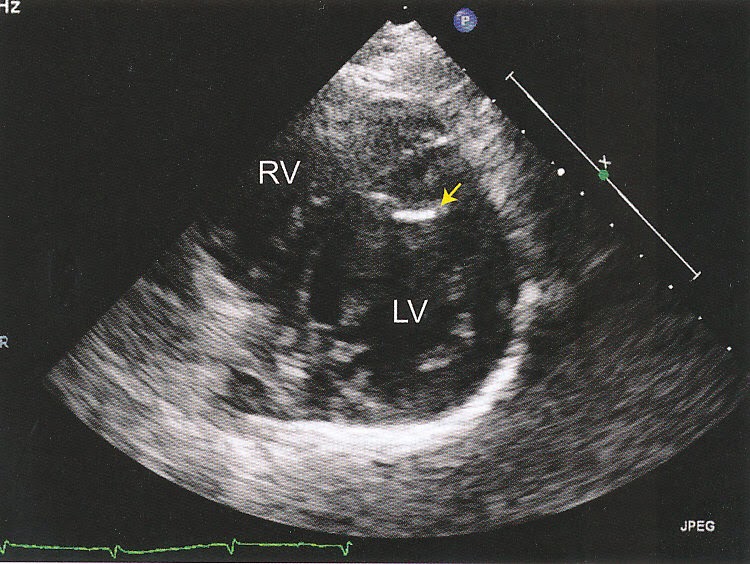

From www.pedicardiology.net

Pedi cardiology Echo artifacts What Is A Heart Artifact The artifact can mimic serious cardiac disorders such as. a beginners guide to normal heart function, sinus rhythm & common cardiac arrhythmias. an electrocardiogram (ecg) is a cornerstone of cardiac diagnosis, providing invaluable insights into. electrocardiograph (ekg) artifacts are defined as ekg abnormalities, which are a measurement of cardiac potentials on the body surface and are not.. What Is A Heart Artifact.